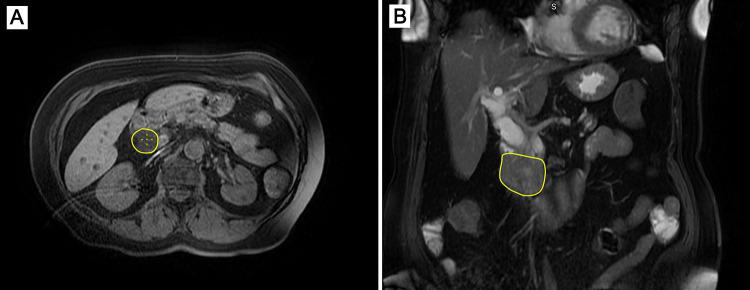

Major abdominal surgeries including pancreatic resection are rarely performed in patients on chronic dialysis due to perioperative morbidity associated with end-stage renal disease. This case report presents a 71-year-old female on hemodialysis with pancreatic head cancer who underwent successful pancreaticoduodenectomy. The patient had the following severe comorbidities: type 2 diabetes mellitus, hypertension, and chronic kidney disease. Therefore, meticulous preoperative preparation, intraoperative care and postoperative management including hemodialysis and nutritional support were performed. Postoperative recovery was uneventful, bowel function was restored on day 5, and the patient was discharged in good condition. This case provides the feasibility of pancreaticoduodenectomy (also known as Whipple procedure) in carefully monitored patients, particularly those on dialysis, despite the increased risk of complications like cardiovascular, immune, and coagulation disorders. Brief literature review confirms that patients with end-stage renal disease can be considered for abdominal surgery with acceptable morbidity and mortality in complex surgical procedures.

由于与终末期肾病相关的围手术期发病率,包括胰腺切除术在内的大型腹部手术很少在接受慢性透析的患者中进行。本病例报告介绍了一名71岁接受血液透析的女性胰腺癌患者,该患者成功接受了胰十二指肠切除术。该患者有以下严重合并症:2型糖尿病、高血压和慢性肾病。因此,进行了细致的术前准备、术中护理以及包括血液透析和营养支持在内的术后管理。术后恢复顺利,第5天肠道功能恢复,患者康复出院。本病例表明,尽管存在心血管、免疫和凝血障碍等并发症风险增加的情况,但在密切监测的患者中,尤其是透析患者,实施胰十二指肠切除术(也称为惠普尔手术)是可行的。简要文献回顾证实,对于终末期肾病患者,在复杂手术中可考虑进行腹部手术,其发病率和死亡率在可接受范围内。